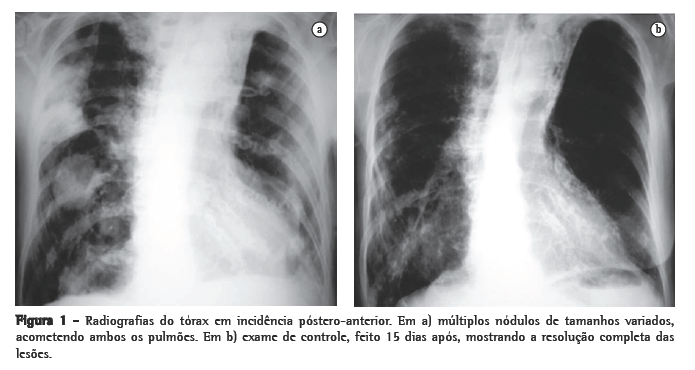

Mulher, branca, 89 anos, com DPOC e relato de bronquiectasias no lobo superior esquerdo há pelo menos 20 anos. O diagnóstico funcional de DOPC foi realizado pelo resultado da relação volume expiratório forçado no primeiro segundo/capacidade vital forçada de 41,2% após o uso de broncodilatador na prova de função pulmonar. Usava diariamente brometo de tiotrópio, b2-agonista de longa duração, associado a corticosteróide inalatório desde setembro de 2004; nas exacerbações agudas, utilizava corticosteróide sistêmico associado a antibiótico de largo espectro. Há 5 dias iniciou quadro de tosse com secreção purulenta, febre de 38 °C, sudorese noturna, prostração intensa, dispnéia e anorexia. Foi prescrito ciprofloxacina por 10 dias, sem melhora clínica, tendo sido internada por 10 dias pelo agravamento do quadro clínico. Nessa primeira internação, a radiografia de tórax mostrava espessamento de paredes brônquicas, pequenas opacidades mal definidas nos lobos superior e inferior direitos e atelectasia com bronquiectasias no lobo superior esquerdo. Foi isolada Klebsiella pneumoniae pela cultura do escarro, e prescrito ceftriaxone, piperacilina/tazobactan. Obteve alta com melhora da febre e da tosse. Em casa, houve recidiva dos sintomas com piora da dispnéia. Realizada radiografia do tórax no domicílio, com aparelho portátil, que mostrou imagens nodulares disseminadas nos pulmões, motivando uma segunda internação (Figura 1). Ao exame apresentava fácies de sofrimento; prostrada; hipocorada; taquipnéica (44 ciclos/min); ­taquicárdica (120 bpm); temperatura axilar, 37 °C; pressão arterial, 120/80 mmHg; e saturação periférica de oxigênio, 84% em ar ambiente. Roncos em ambos os pulmões.

Inicialmente foi prescrita a associação sulfametoxazol e trimetoprima, sem resposta clínica. Foram então prescritas amicacina associada a Imipenem/cilastatina por 15 dias, com excelente resposta clínica e radiológica (Figura 1). Recebeu alta hospitalar com prescrição de sulfametoxazol e trimetoprima por mais 8 semanas.

Nódulos, massas escavadas, derrame pleural, pneumotórax, opacidades em vidro fosco e padrões intersticiais podem também ocorrer.(1,4,5,11) Alguns estudos mostram que, em pacientes HIV positivos, existe um percentual maior de lesões escavadas.(8) A consolidação alveolar nos lobos superiores é muitas vezes confundida com tuberculose pulmonar.(6) Embora as alterações vistas na TC sejam ­semelhantes às das radiografias convencionais, a TC é superior na demonstração da exata localização e extensão das lesões, assim como na diferenciação entre lesões pulmonares e pleurais.(5) No caso relatado, a paciente apresentava imagens nodulares de tamanhos variados, disseminadas por ambos os pulmões, e algumas delas escavadas.